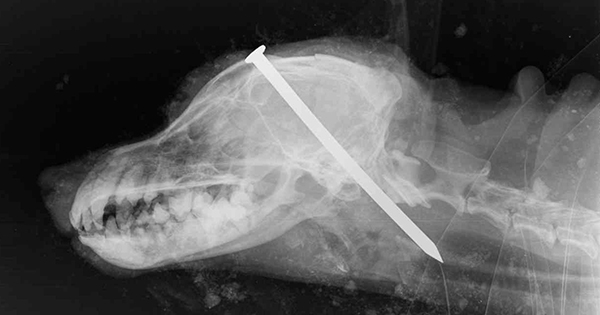

狗狗从远古时代就一直陪伴着人类,一直到现代都还是被视为人类最忠心的伙伴。然而在英国却有一位狠心的饲主,将自己养了16年的老狗狠用铁钉钉入脑中后活埋,但最扯的其实是他事后…